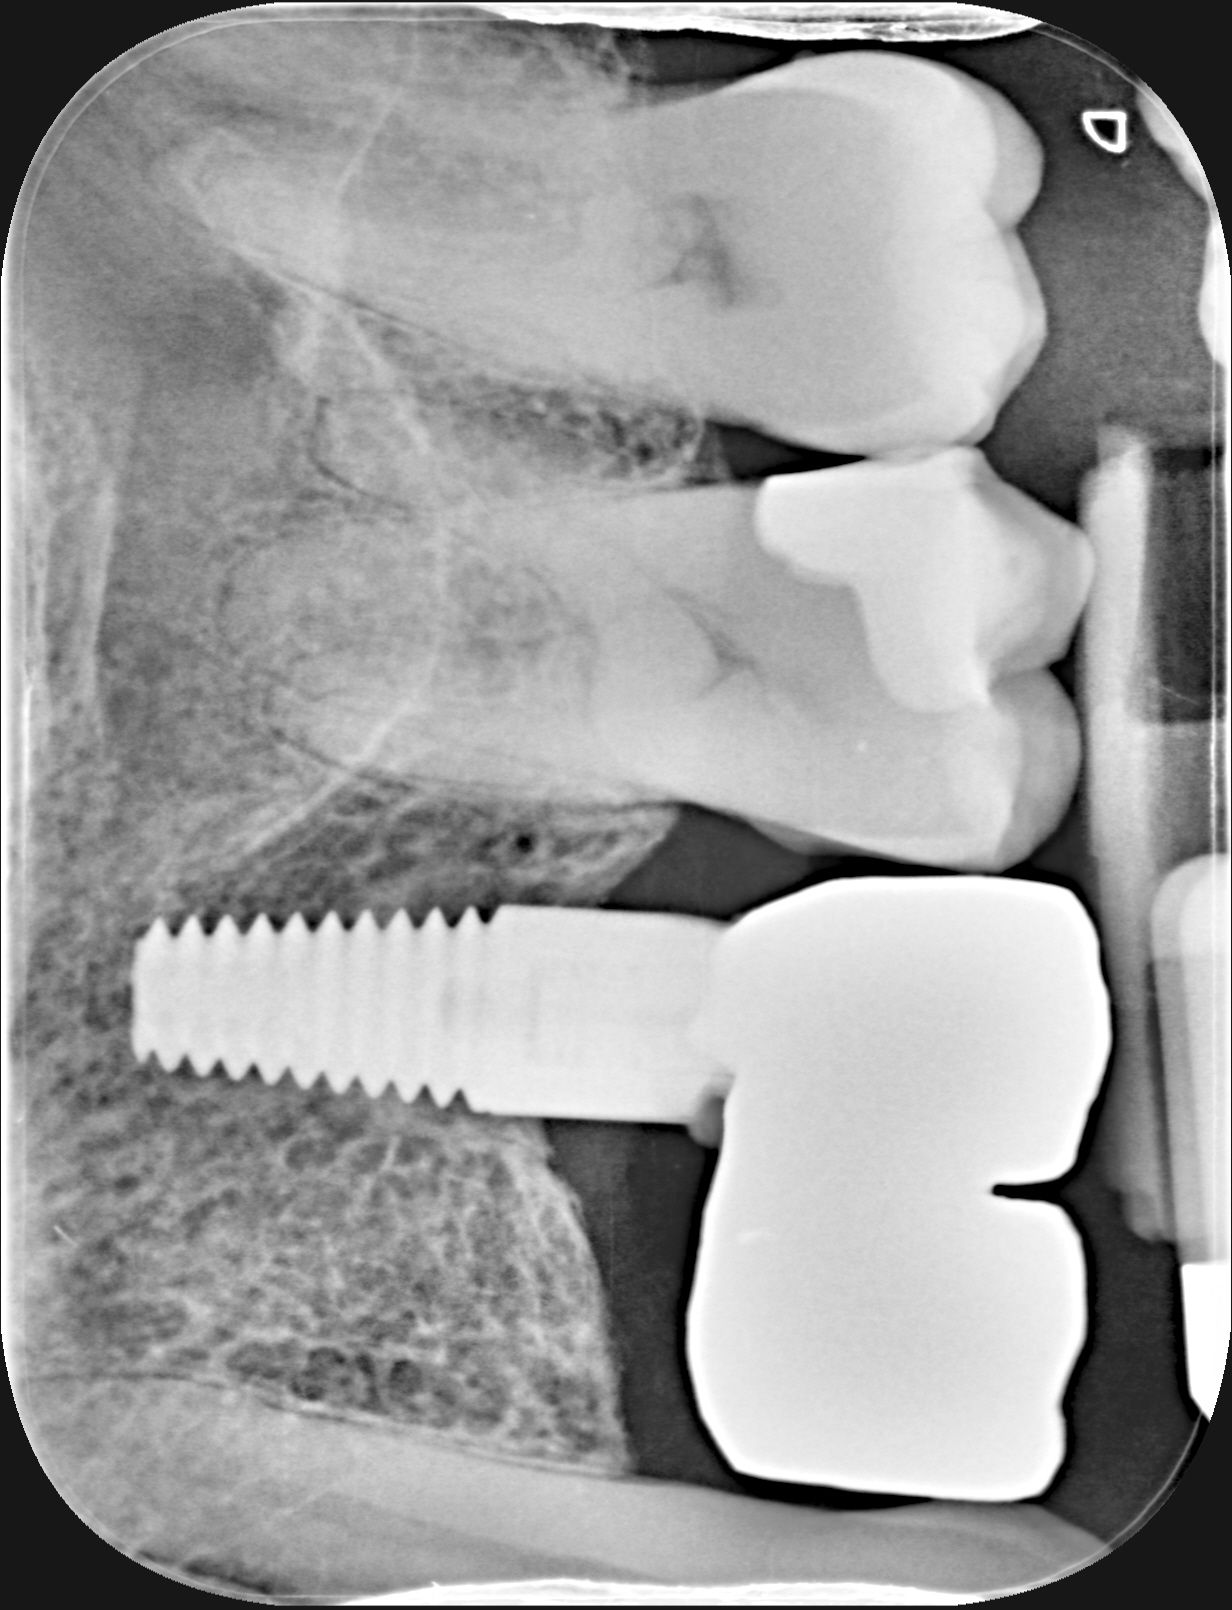

Thanks, could be rct but I get pain both with hot and cold if that makes difference, cold worse than hot, nothing is visable in xray, the tooth has a had a filling though, replaced a year or so ago because it leaking. The tooth they think it is is one behind implant, this is xray from when pain first started, it 1st molar, one thing 2nd dentist noticed was signficant widening of the periodontal ligament, and they mentioned 'irreversible pulpitis' as well. I have xrays from 6 years ago of same tooth and the widening seems signficant.Pain that: